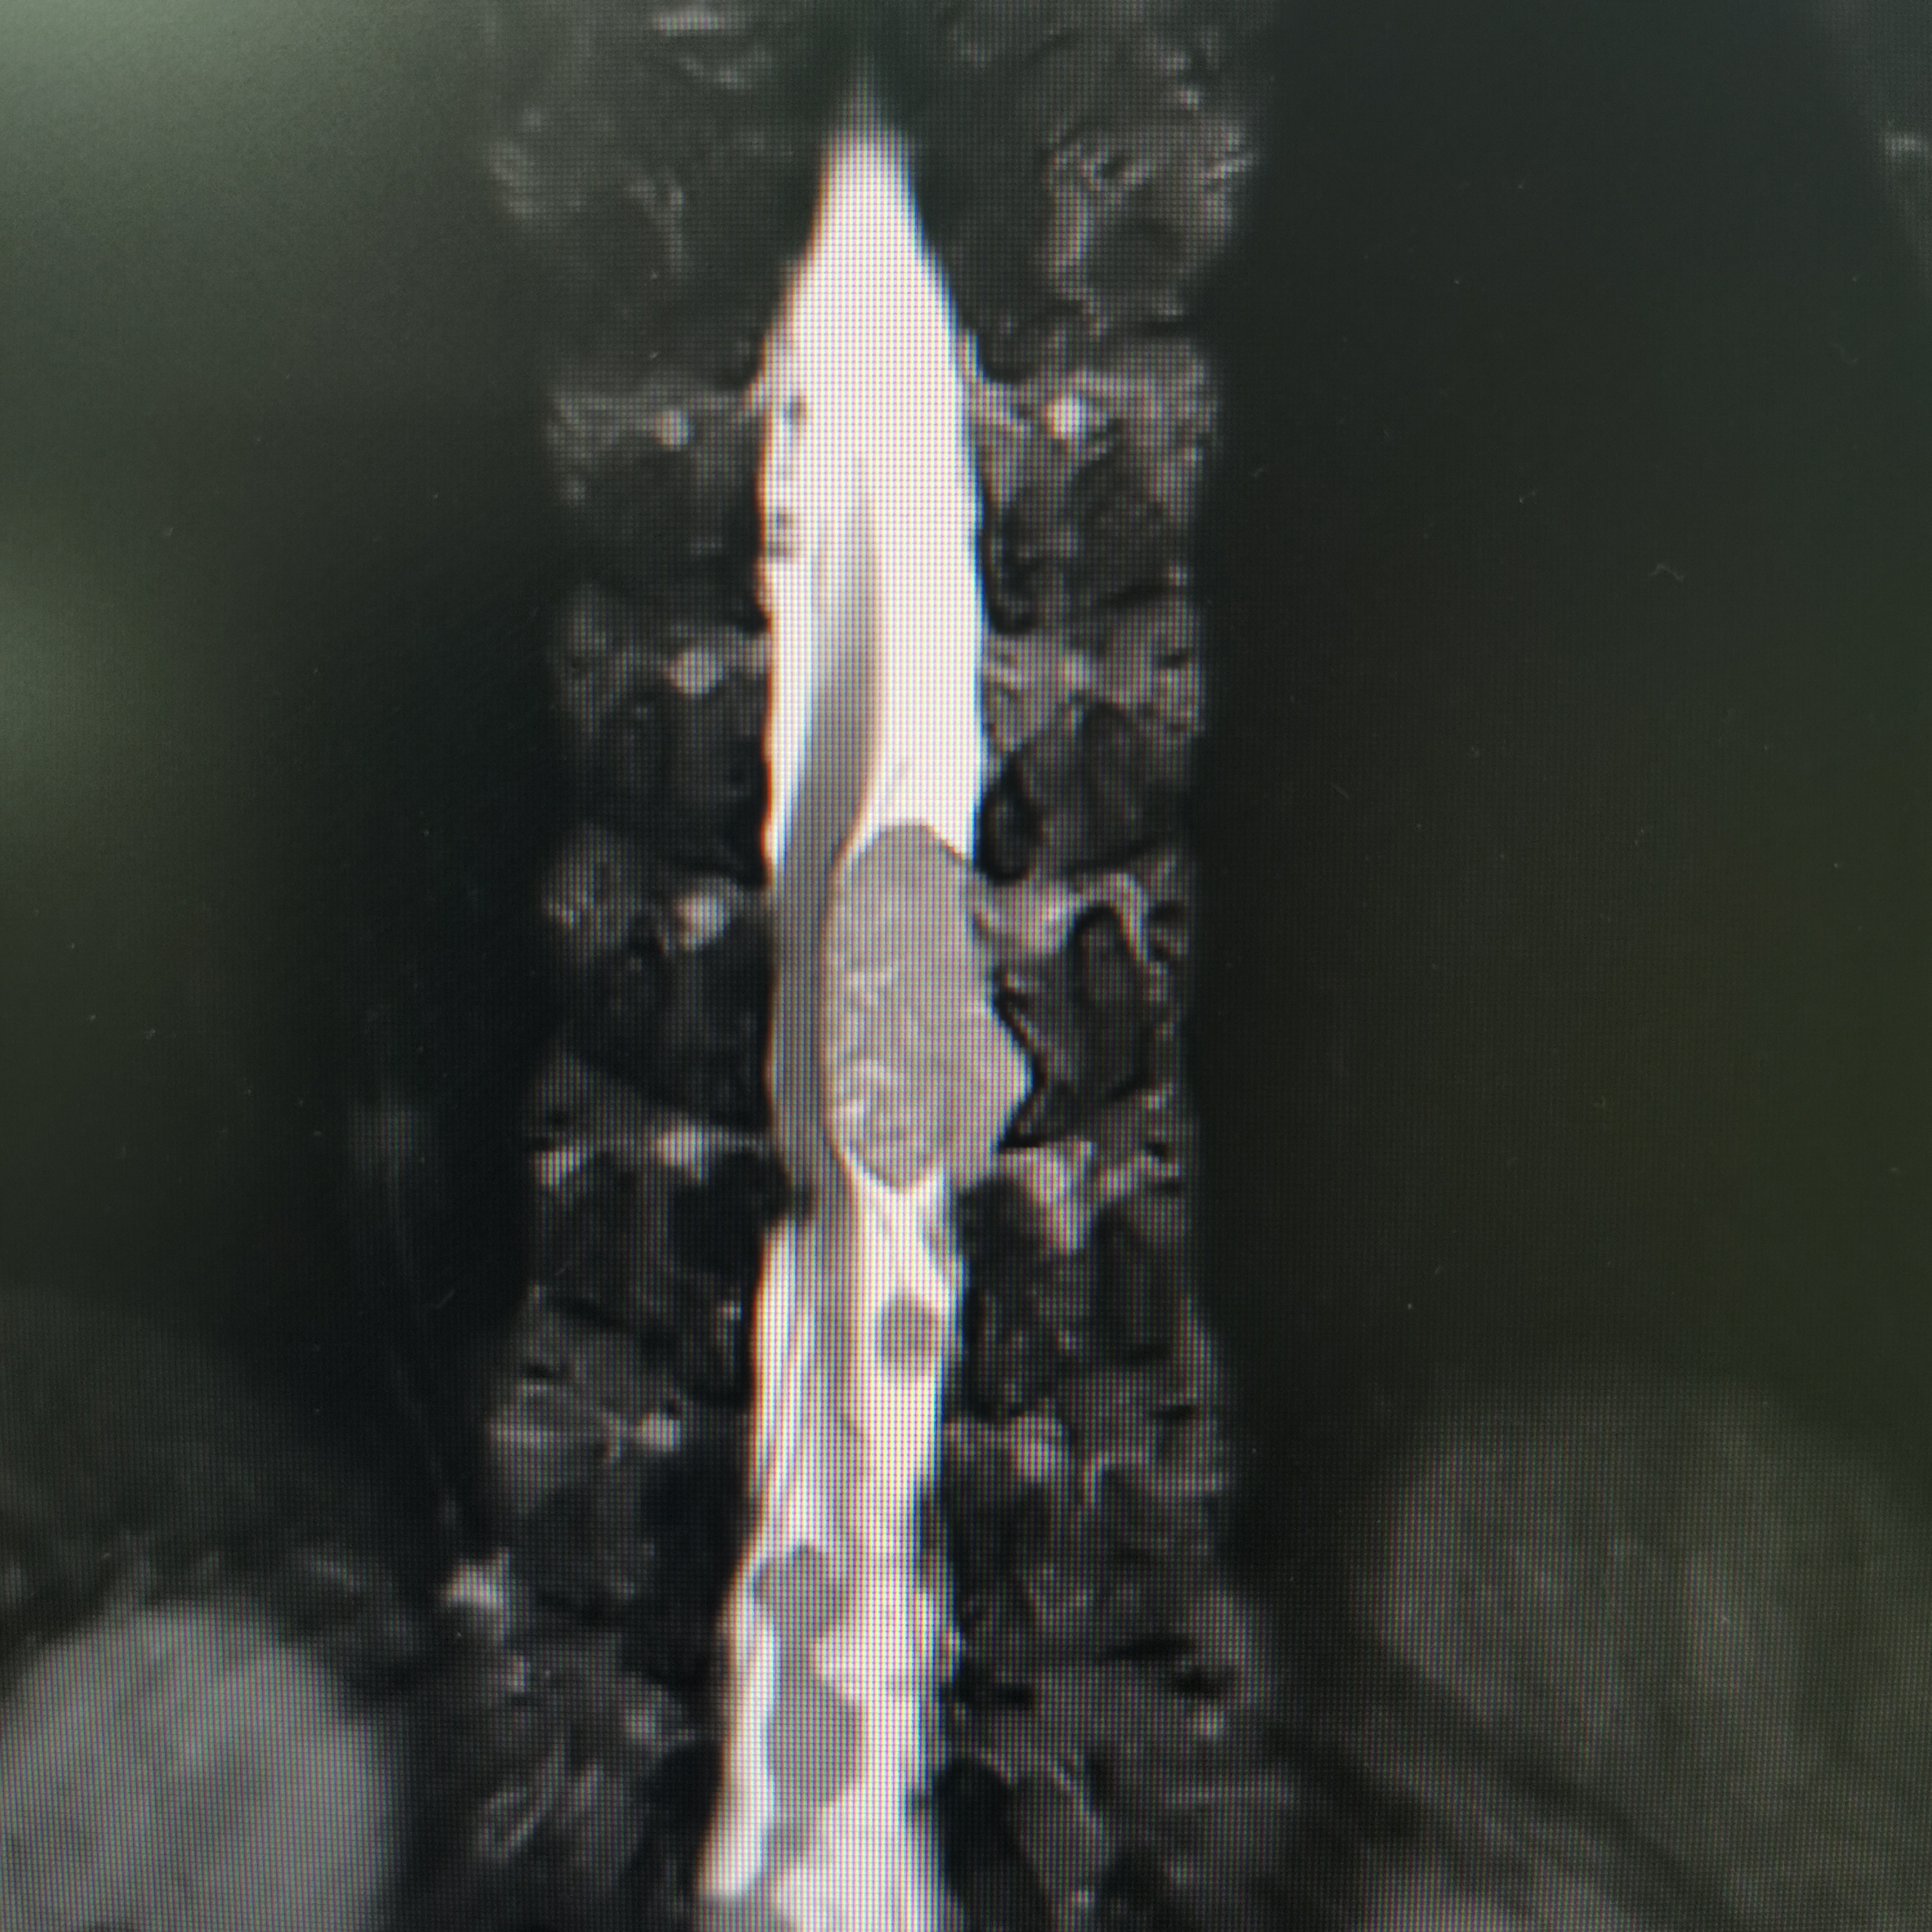

脊髓脊柱-脊髓脊柱肿瘤

神经纤维瘤病的治疗需要综合考虑患者的病情、症状、年龄、身体状况等因素,制定个性化的治疗方案。